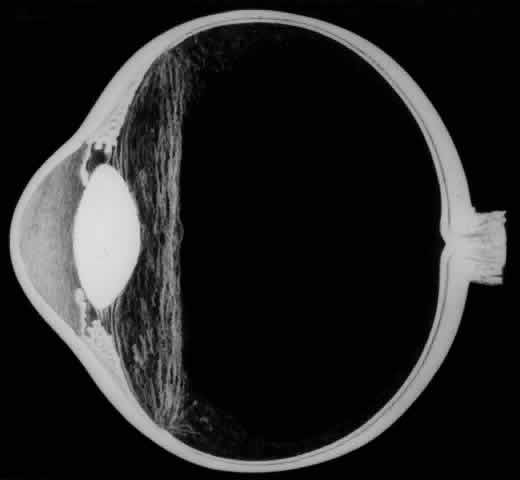

Biomicroscopic Findings Preceding Development of a Giant Tear

The earliest biomicroscopic changes preceding the development of a giant retinal tear were syneresis and liquefaction of the vitreous gel, converting the posterior and central portions of the vitreous body into a large lacuna (Fig. 14). Later, the anterior gel became condensed, and its posterior aspect formed an equatorially oriented membrane extending across the vitreous cavity (Fig. 15). This membrane did not oscillate with ocular movements, suggesting that it was under tension. Marked contraction of this membrane seems responsible for tearing the retina along the posterior border of the vitreous base (Fig. 16). Liquefied vitreous gel facilitated inversion of the posterior retinal flap (Fig. 17).

Fig. 15. In later biomicroscopic changes preceding a nontraumatic giant retinal break, the anterior vitreous gel becomes condensed and a membrane forms its posterior aspect.

Fig. 16. Contraction of this equatorially oriented membrane extending across the vitreous cavity produces a giant tear along the posterior border of the vitreous base.

Fig. 17. After the formation of a giant retinal tear, the posterior retinal flap inverts into the liquefied vitreous (arrow).